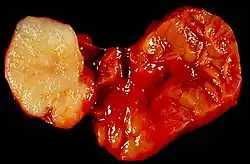

![]() Guz ślinianki przyusznej |

Gruczoły ślinowe mogą stać się siedliskiem różnorodnych zmian nowotworowych. Większość rozwija się w szóstej lub siódmej dekadzie życia z taką samą częstotliwością u obu płci. W śliniance przyusznej 70–80% nowotworów to zmiany łagodne, w podżuchwowej ponad połowa jest złośliwa.